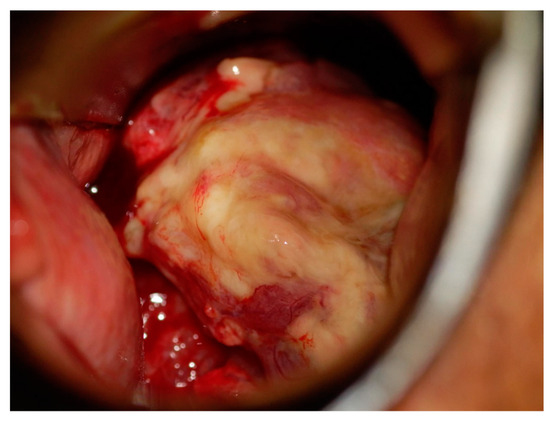

Figure 1.

Colposcopy of the cervix. A bulky tumor occupying the vagina, and the tumor was diagnosed as macroscopic invasive carcinoma.